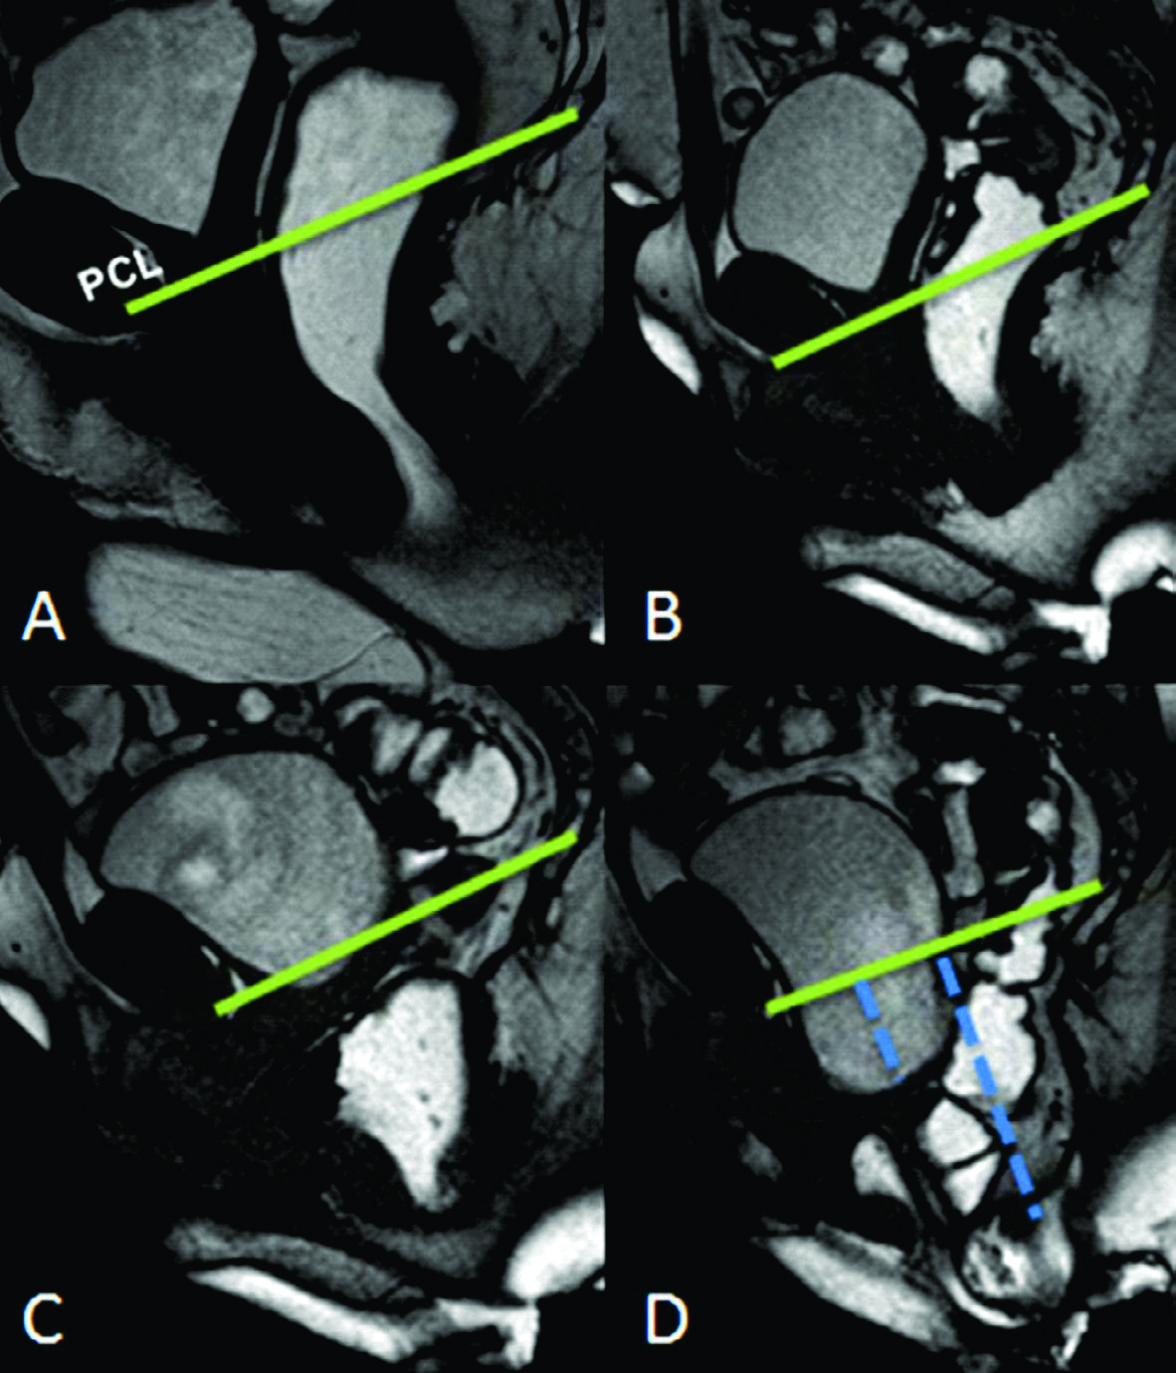

Figura 10

Rectocele eversión

A) Imágenes potenciadas en T2 de alta resolución en el plano sagital a nivel de la línea media de una mujer durante el reposo.

B) TRUE FISP sagital durante maniobra de Valsalva.

C-D) TRUE FISP sagital durante defecación. Se evidencia cistocele, prolapso vaginal y eversión del recto. Las líneas punteadas azules cuantifican la severidad de los prolapsos.